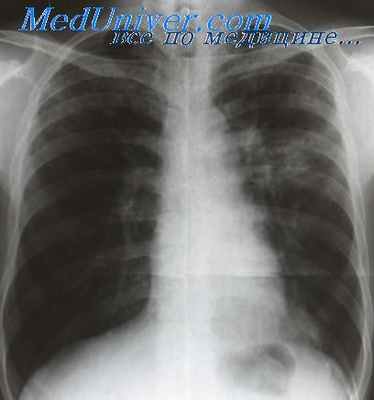

Очень информативно при экссудативном плеврите рентге нологическое и ультразвуковое исследование. По мере накоп ления экссудата исчезает прозрачность в области ребернодиафрагмального синуса и тень жидкости выявляется над диа фрагмой (рис. 16.1). При увеличении объема жидкости в вер тикальном положении больного обнаруживают типичную для свободного экссудата картину затемнения нижних отделов ле гочного поля с параболической верхней границей, идущей сверху снаружи — вниз и внутрь. Тень экссудата бывает ин тенсивной и однородной. При значительном объеме жидкости органы средостения смещаются в противоположную сторону (рис. 16.2). Свободный плевральный выпот хорошо определя ется при ультразвуковом исследовании (УЗИ) и на КТ — жид-

Рис. 16.1. Туберкулезный экссудативный плеврит справа. Рентгено грамма легких в прямой проекции.

Рис. 16.2. Туберкулезный экссудативный плеврит слева. Смещение органов средостения в правую сторону.